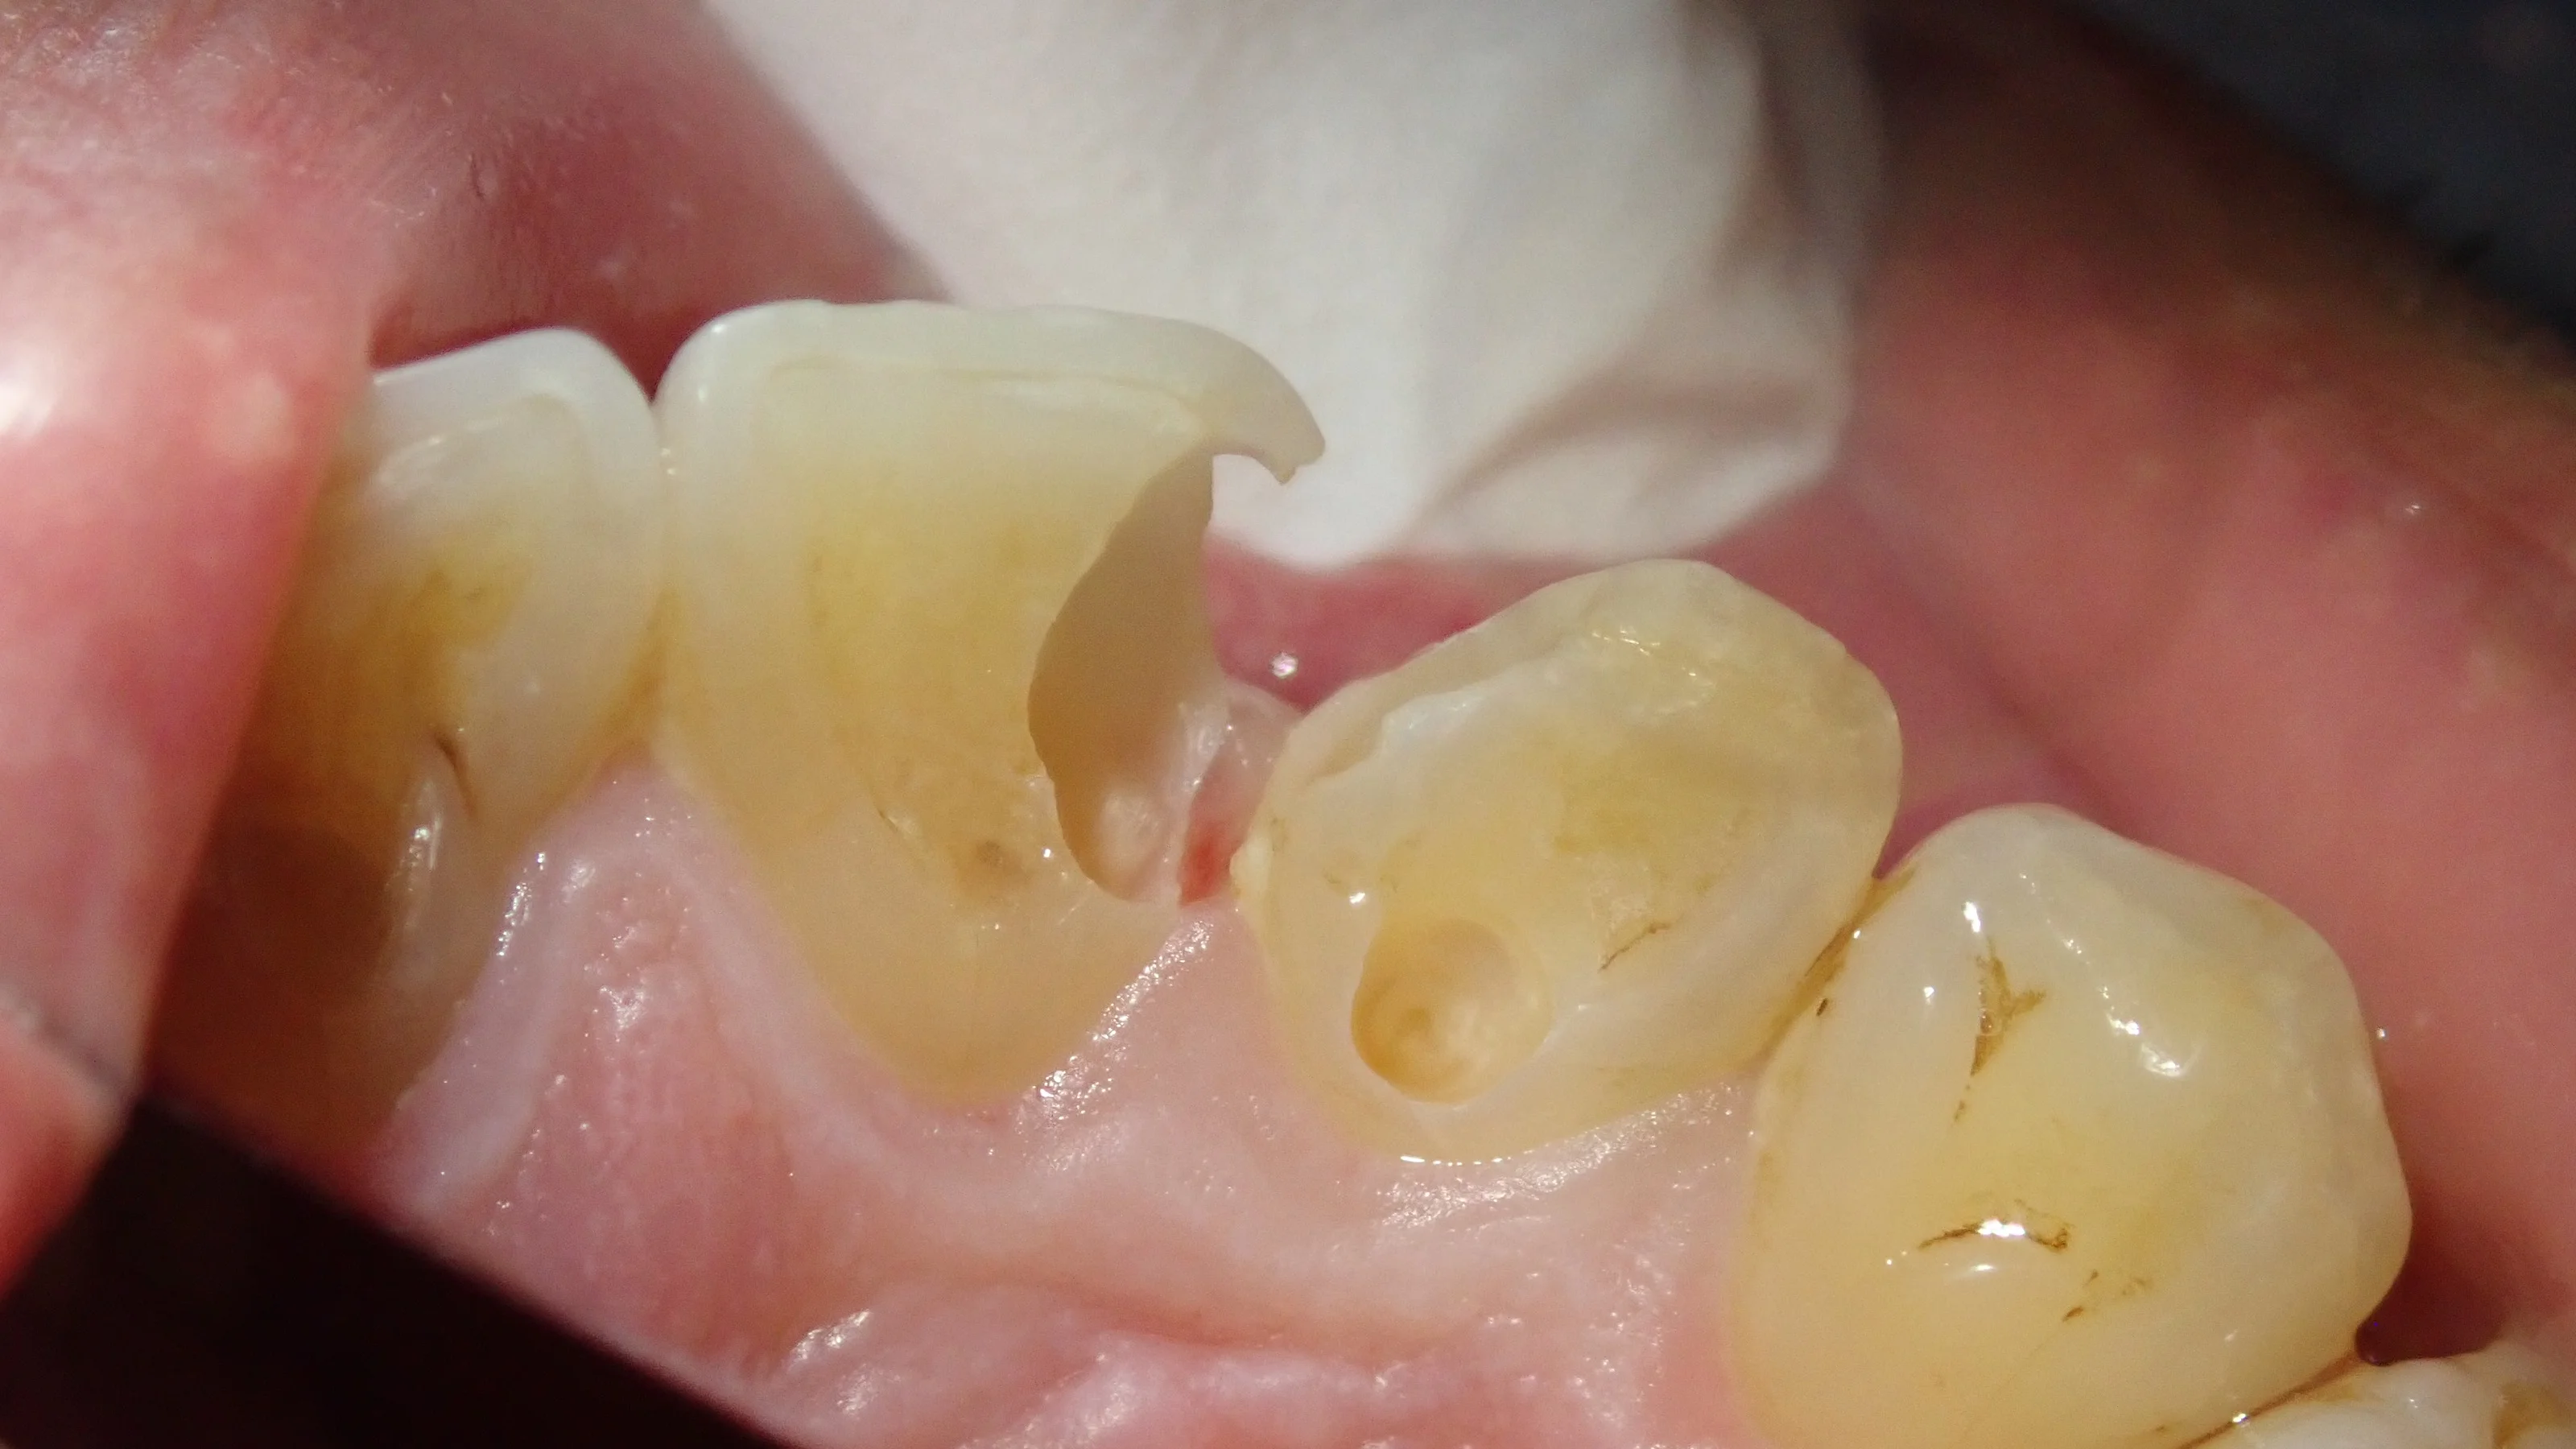

で、虫歯を取りきった時の写真がこちらです。

表面と、

裏面です。

やはり適切な時期に治療に介入できなかったのは痛いですね。

歯の半分くらいは人工物になってしまいます。

ここまで大きくなると、次虫歯の治療を行うときには間違いなく被せ物になってしまいますね。